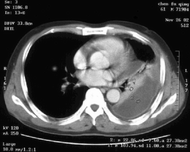

惡性胸腔積液CT圖發病機制:

惡性胸腔積液CT圖1.最常見的致病因素 是壁層和(或)髒層胸膜腫瘤轉移。這些轉移瘤破壞毛細血管從而導致液體或血漏出,常引起血性胸腔積液。